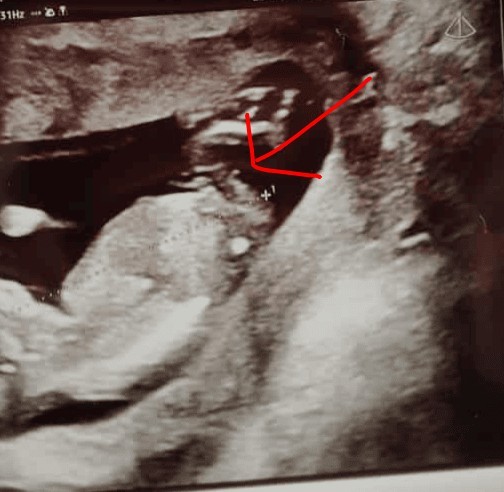

Czy można sterdzil po tym zdjęciu jaka płeć ?

A mogłabyś oznaczyć wyrostek na zdjęciu ?Hmmm słabe ujęcie - ale wydaję mi się,że wyrostek leci płasko - czyli dziewczynka![]()